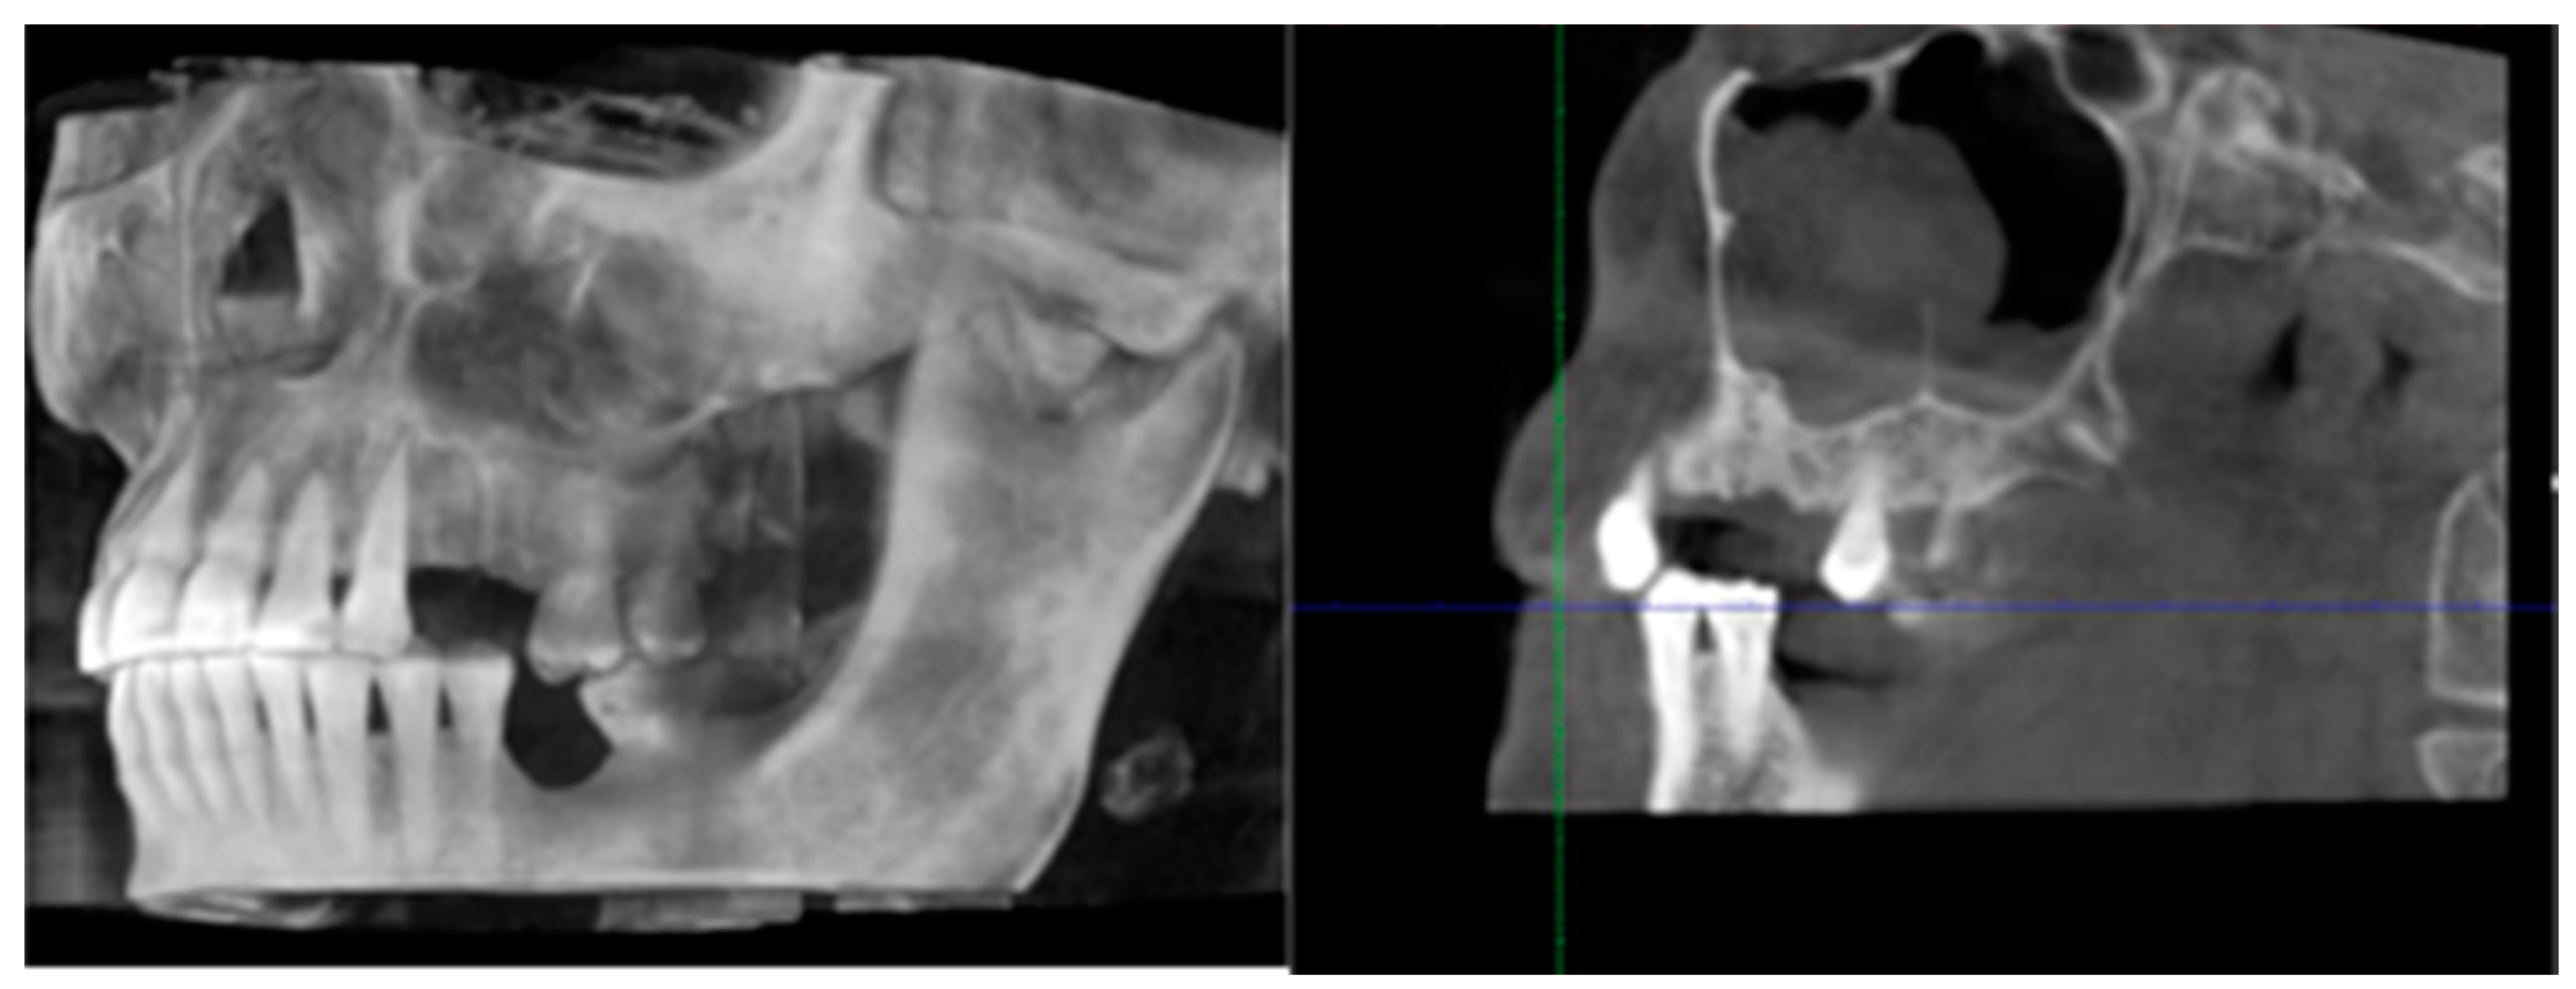

2. Materials and Methods

3. Results

4. Discussion